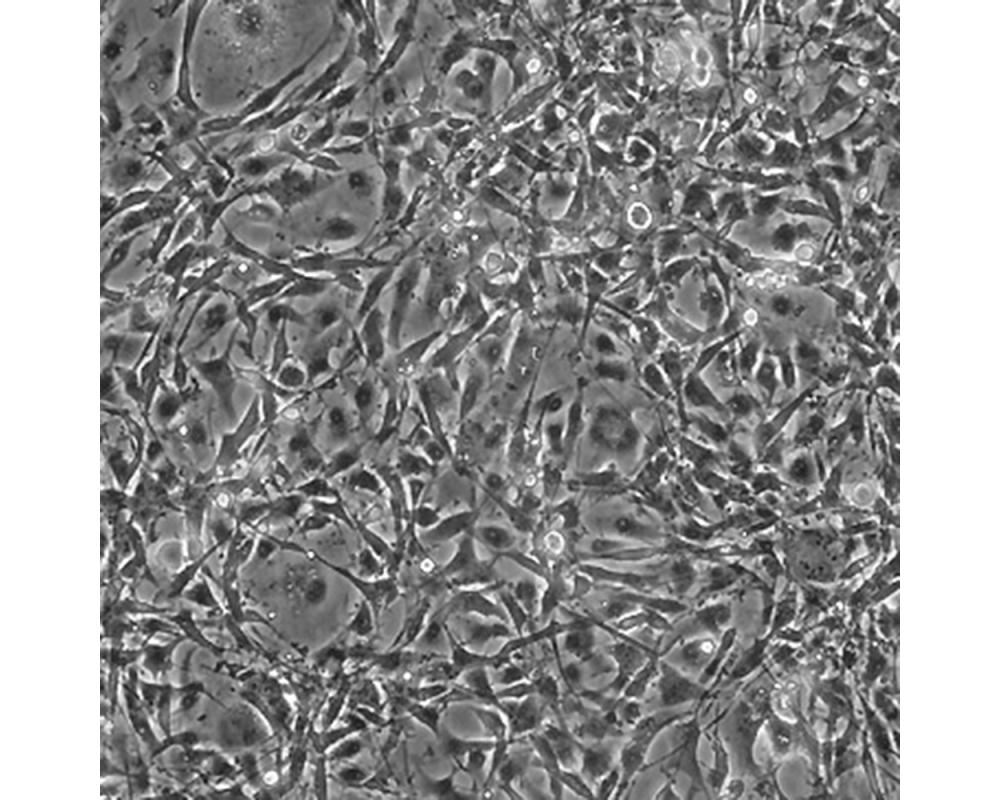

U-118 MG

中文名稱 人腦星形膠質母細胞瘤

組織來源 星形膠質母細胞瘤;男性

生長特性 adherent

形態特征 mixed